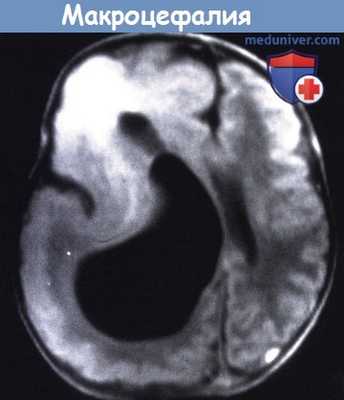

Т1 - взвешенное изображение МРТ пациента в возрасте пяти месяцев.

Большое правое полушарие, с патологически утолщенной корой и несколькими бороздами.

Значительно увеличенный желудочек и аномальный сигнал от лобного белого вещества.

(а) МРТ, Т1-ВИ, аксиальный срез: у этого же пациента определяется увеличение размеров правого большого полушария с заметным смещением серпа мозги межполушарной борозды влево. Передний рог ипсилатерального бокового желудочка заострен. Кроме того, наблюдается понижение сигнала от БВ измененного полушария.

(б) МРТ, Т2-ВИ, аксиальный срез: у этого же пациента определяется увеличение объема БВ правого полушария и повышение сигнала от него по сравнению с противоположной стороной. Визуализируются диспластичность вышележащей коры, а также нечеткость границы между серым и белым веществом. (а) МРТ, последовательность инверсия-восстановление (IR), аксиальный срез: аномальная морфология коры всего полушария. Определяется полимикроги-рия лобной и височной областей, в то время как кора теменной и затылочной областей утолщена, а извилины сглажены.